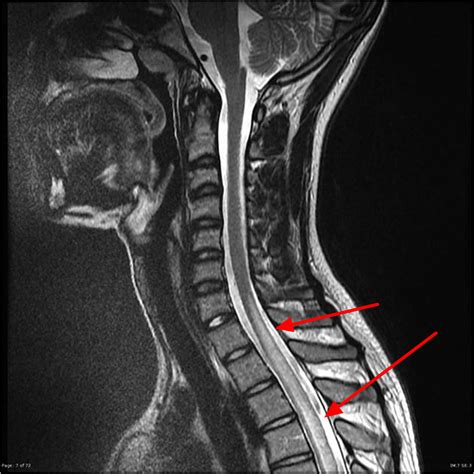

The urgency of Transverse Myelitis treatment cannot be overstated. When a patient presents with symptoms, physicians aim to stop the inflammatory process as quickly as possible. Every hour counts in reducing the potential for permanent nerve damage. Prompt diagnosis through MRI scans and lumbar punctures allows neurologists to initiate therapy, which often changes the trajectory of recovery significantly.

⚠️ Note: Symptoms of Transverse Myelitis can mimic other neurological conditions, such as Multiple Sclerosis or Neuromyelitis Optica. Early diagnostic imaging is essential to ensure the correct treatment plan is followed.